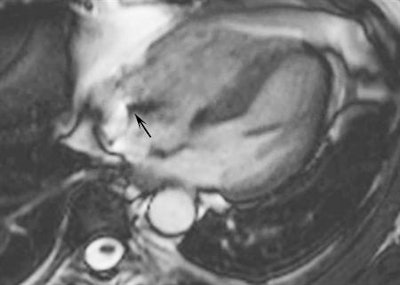

![Cardiac MR of a 59-year old patient carrying an implantable cardioverter defibrillator (ICD). The cine steady state with free precession sequence (time of repetition [TR] 50 ms, time to echo [TE] 3.3 ms, flip angle 80°) acquired along the four-chamber view (a) was largely impaired by a large concentric artifact (asterisk in a) not allowing for segmenting both ventricles. The corresponding cine gradient echo fast low-angle shot sequence (b) (TR 49 ms, TE 1.5 ms, flip angle 15°) shows a strongly reduced artifact generated by the ICD not impairing the evaluation of both ventricles. The artifact generated by the electro-catheter is visible in the right atrium in both images (white arrows in a and b). Image courtesy of Moreno Zanardo.](https://img.auntminnieeurope.com/files/base/smg/all/image/2017/11/ame.2017_11_15_16_20_6001_2017_11_13_MRI_insider_pic11_20171115163055.png?auto=format%2Ccompress&fit=max&q=70&w=400)